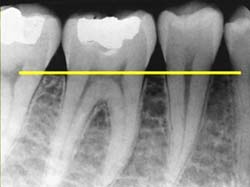

歯周病の原因は、歯に付着したプラーク(歯垢)に含まれる「歯周病菌」が、歯周組織を次々に破壊し骨まで溶かしてしまう病気です。歯周病は、症状が進むまで痛みもほとんど発生しないため、気がついたら既に手遅れとなっており、歯を支える骨(歯槽骨)が溶けてしまい、歯を失ってしまいます。

歯肉炎→歯周病(第1段階→第2段階→第3段階)